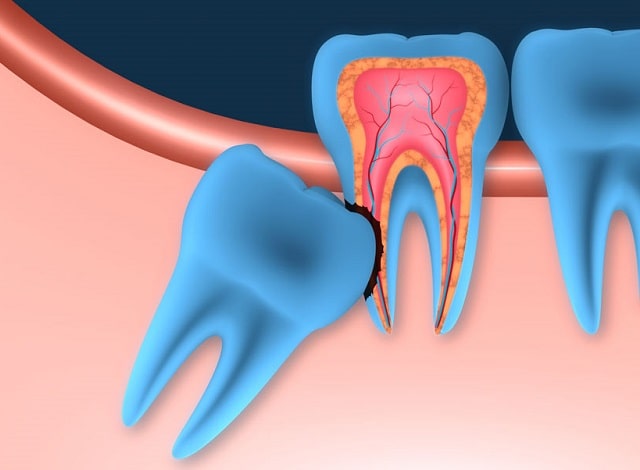

- разрушение корней рядом стоящих зубов;

Особенно опасна частичная ретенция: участок зуба, прорезавшийся наружу, контактирует со слюной и бактериями, что часто вызывает перикоронарит — воспаление окружающих тканей.

Без лечения ретенция может привести к таким последствиям:

- смещение соседних зубов;

- деформация прикуса;